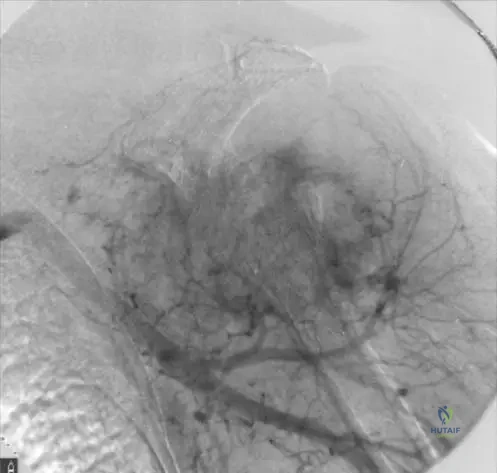

A 16-year-old male presents with a 3-month history of progressive right distal femur pain, worse with activity and at night. Physical examination reveals a palpable mass and tenderness over the distal femur. Radiographs show a destructive lesion in the distal femoral metaphysis with a sunburst periosteal reaction and Codman's triangle. There is evidence of cortical breach. A chest CT reveals multiple bilateral pulmonary nodules.

Correct Answer: E

Rationale: The clinical presentation and radiographic findings are highly suggestive of osteosarcoma with pulmonary metastases. The initial diagnostic step for a suspected malignant bone tumor is an image-guided core needle biopsy. This provides tissue for definitive diagnosis, grading, and molecular studies while minimizing contamination of surrounding tissues, which is crucial for subsequent limb salvage planning. An open biopsy is generally avoided due to increased risk of contamination and potential compromise of future surgical margins. Neoadjuvant chemotherapy is indicated after a definitive diagnosis is made. Excisional biopsy of lung nodules is not the primary diagnostic step for the bone lesion. Palliative radiation is not the initial treatment for potentially curable metastatic osteosarcoma.